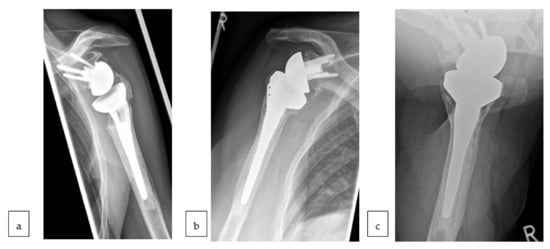

2.2. Surgical Technique and Rehabilitation Protocol